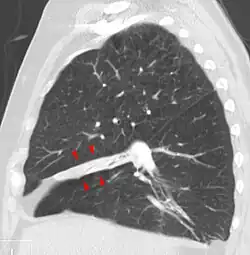

O colapso pode ser detectado por[2]:

- Tomografia computadorizada;